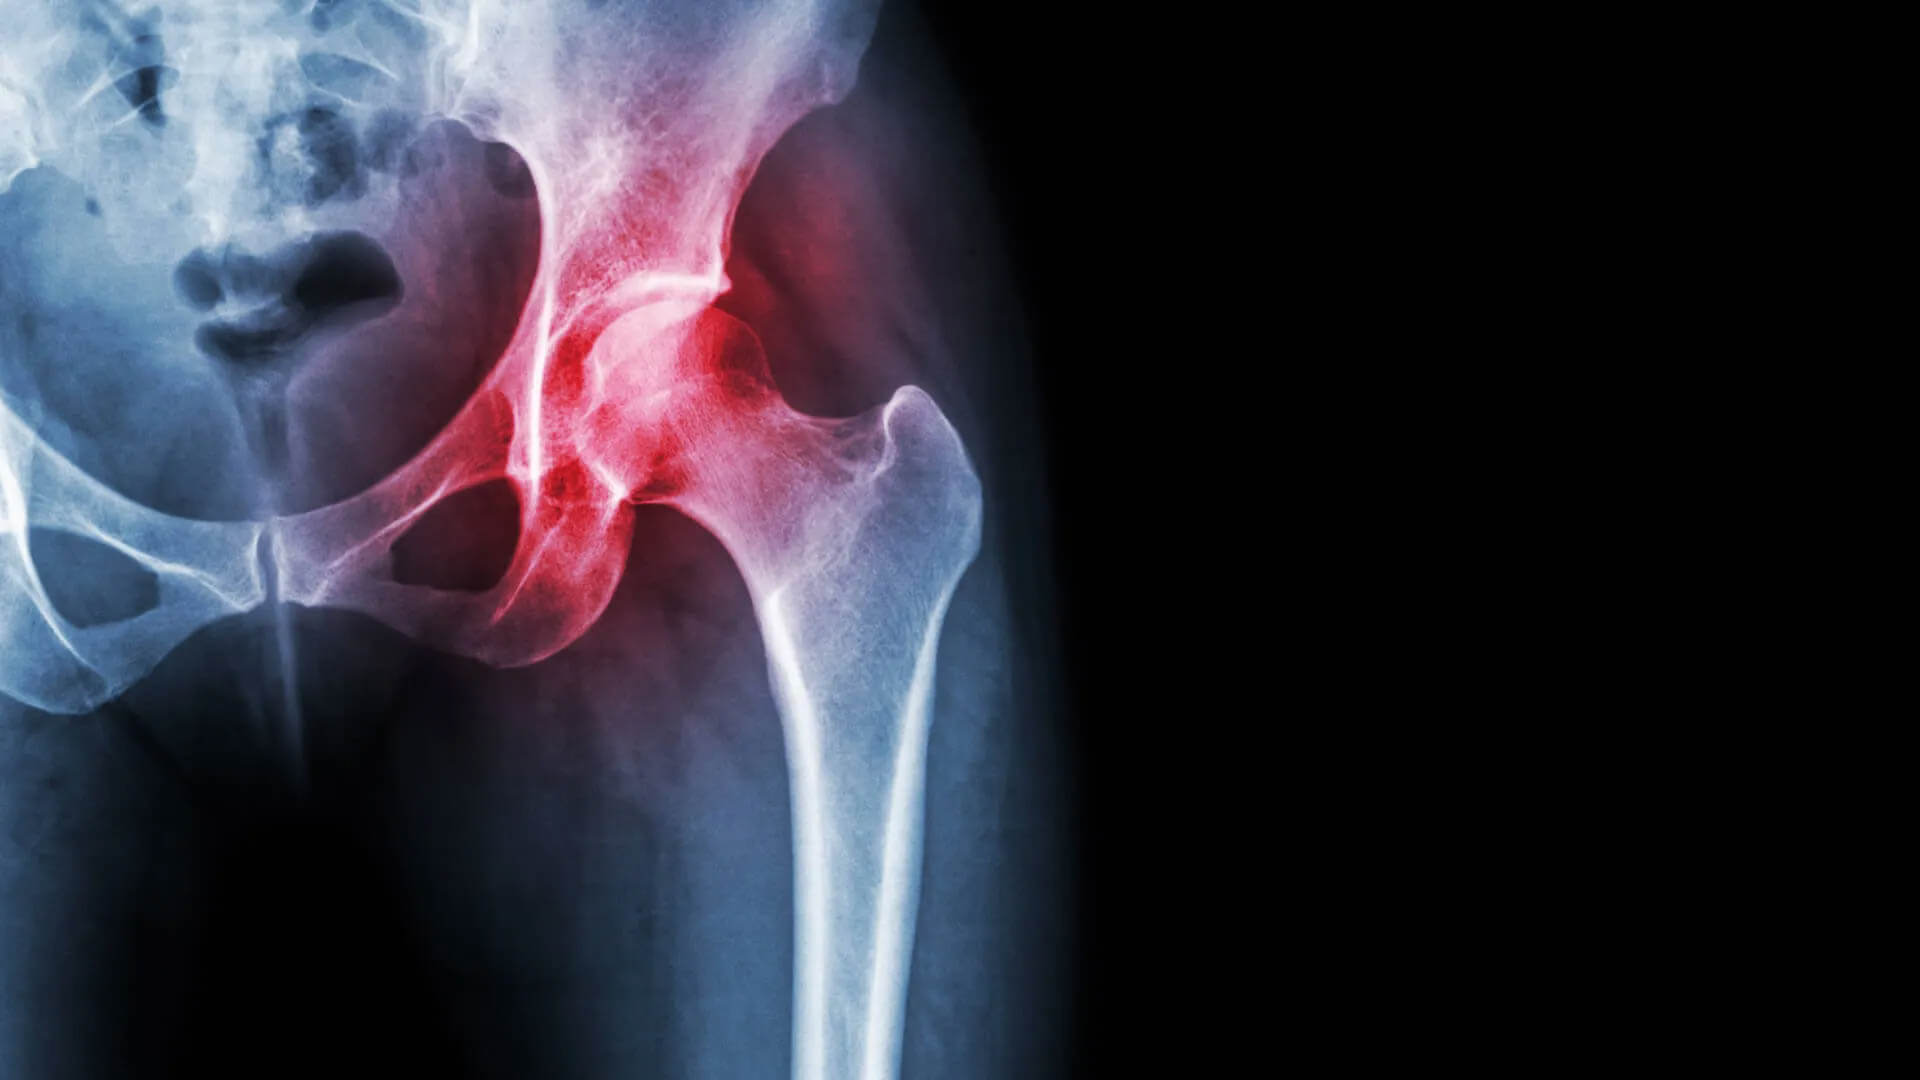

Arthritis And Hip Replacement . if your hip has been damaged by arthritis, a fracture, or other conditions, common activities such as walking or getting in and out of a chair may be painful. arthritis is the most common cause of hip pain and other symptoms that lead to people needing a hip replacement. what you need to know. During a hip replacement surgery, an orthopaedic surgeon replaces both ends or one end of the damaged hip joint with artificial parts. if you’re in pain or it has become hard to move around, hip replacement surgery may seem like a no. Hip replacement can address hip pain and stiffness for people with arthritis, avascular necrosis or other forms of hip joint damage. also called total hip arthroplasty, hip replacement surgery might be an option if hip pain interferes with.